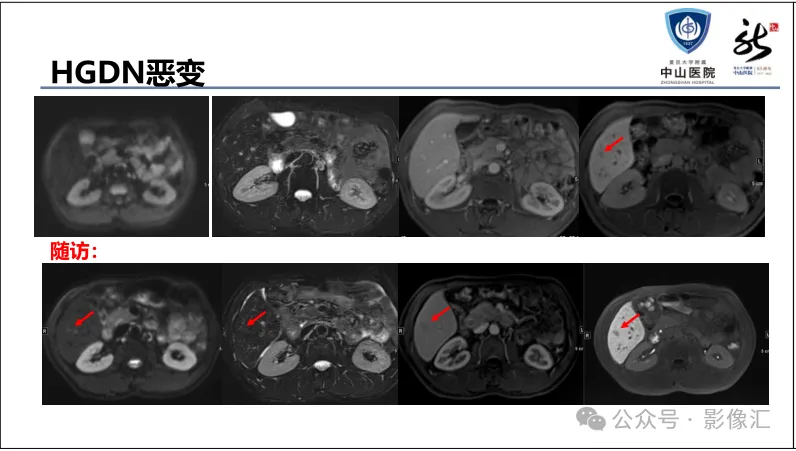

肝胆特异性对比剂增强肝胆图像判读方法与策略,课件来源于网络,作者复旦大学附属中山医院放射科饶圣祥教授。